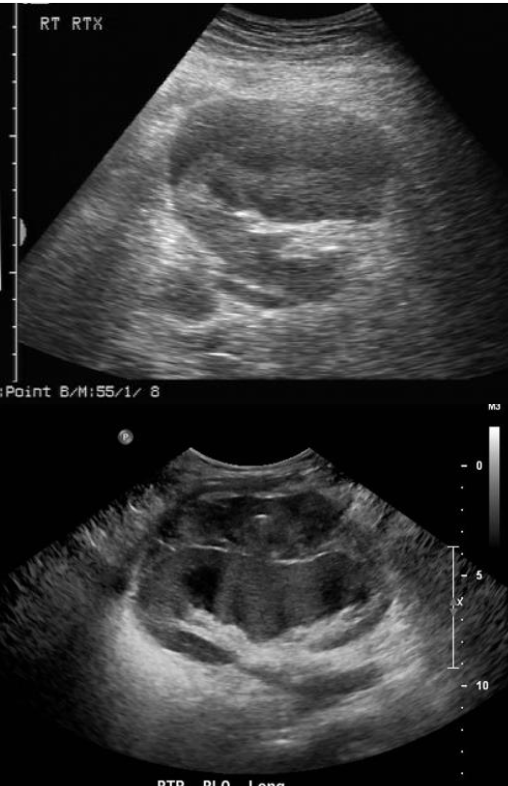

Hydronephrosis → dilation of renal collecting system from mechanical obstruction or functional dysfunction (calculi, mass, trauma, pregnancy)

clinical hx: prone to stones (stasis, pregnancy)

s/sx: if stone → renal colic, N&V, hematuria, frequency/urgency

2D US: grade 1 (mild) → pelviectasis, cortex preserved, grade 2 (mild to moderate) → expands into major calyces, cortex preserved, grade 3 (moderate) → expand all calyces, entire pelvis dilated, cortex preserved, grade 4 (severe) → cortical thinning, AKI to CKD, creatinine >1.2

color doppler: avascular

DDX: parapelvic cysts